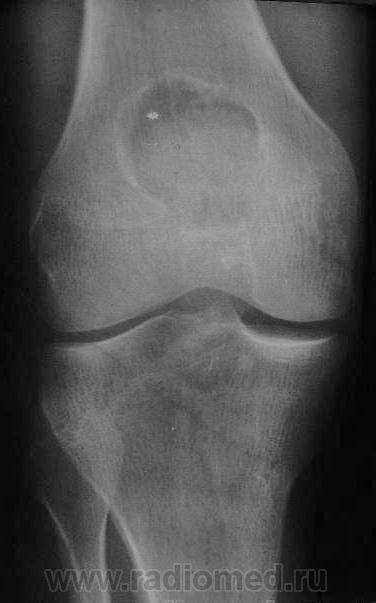

Здравствуйте, уважаемые коллеги! Сегодня в травмпункте принесли на описание снимки молодого человека 1984г.р. Травма, подвернул ногу. Жалобы характерные. Не наблюдался, не лечился. Прошу высказать мнение о характере патологии в метафизе бедренной кости.

Я склоняюсь к ГКО с кортикальным расположением, прорывом содержимого в мягкие ткани. А что думаете Вы? Т.к. снимок из травмпункта, поговорить с больным проблематично (я там совмещаю по вечерам).

На гигантоклеточную опухоль похоже, но не очень

Метафизарный кортикальный очаг фиброзной дисплазии. ИМХО.

какой красивый "козырек" по задней поверхности...

Расположение крупного очага деструкции эксцентрично (кзади) и вкрапления извести говорит в пользу солитарной хондромы, а местами нечеткие контуры ("скорлупа" теряется), "козырек" и  мягкоттканный компонент нацеливают на озлокачествление. Кроме того очень смущает структура прокс. эпиметафиза б/берц. кости. В любом случае, вижу прямые показания к активным действиям, начиная с биопсии.

И я за хондрому.

Спасибо за высказанные мнения. Интенсивная тень в проекции метафиза это артефакт на пленке. Больного я отправил на консультацию в специализированное учреждение, так что потеряться он не должен. Если узнаю результаты, то сообщу.